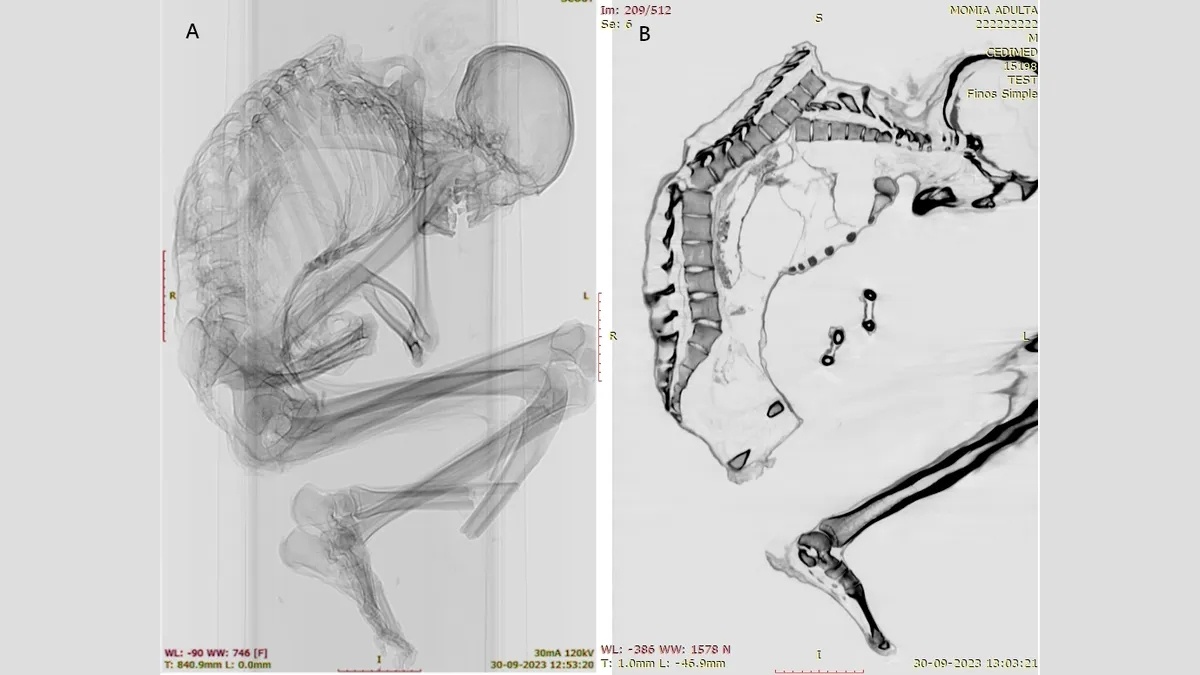

Только в 2023 году ученые провели полный анализ мумии с использованием компьютерной томографии и рентгена, и сейчас опубликовали результаты этого исследования. Анализ выявил обширную травму, ставшую, по-видимому, причиной смерти мужчины.

Исследователи обнаружили у мумии многочисленные незажившие переломы верхней части позвоночника, а также переломы ребер, лопатки и ключицы. Это указывает на сильный удар, пришедшийся на верх спины, при этом «основная сила удара пришлась на верхнюю левую часть грудной клетки». Удар привел к смещению нескольких позвонков и разрушению грудной клетки.

Кроме того, обнаружен перелом основания позвоночника. Подобные повреждения наблюдаются у людей, пострадавших при землетрясениях или при авариях в лесной, строительной и горнодобывающей промышленности. Обычно такие травмы связаны с серьезным повреждением спинного мозга и часто приводят к смерти.

Однако на черепе, шее и руках мужчины не было обнаружено никаких повреждений. Ученые полагают, что мужчина был шахтером, добывавшим бирюзу, и в момент удара активно трудился, нагнувшись, или успел закрыть голову руками, когда на него упал тяжёлый предмет – вероятно, большой камень.